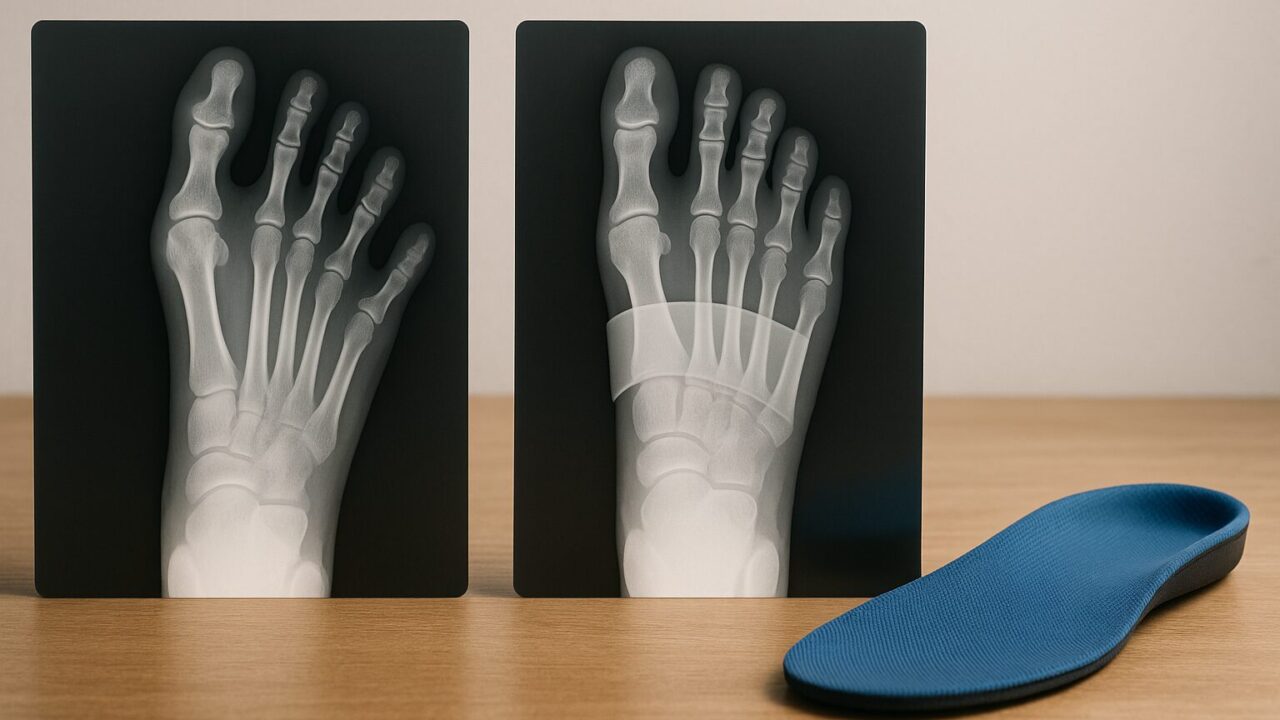

歩くたびに足の裏にピリッとした痛みが走ったり、指の付け根にタコや魚の目ができて悩んでいませんか?それは「開張足(かいちょうそく)」のサインかもしれません。もともとアーチ状になっているはずの、足の指の付け根付近(横アーチ)がつぶれてべったりと地面についてしまう状態で、足の疲労感を増幅させるだけでなく、外反母趾や内反小趾などの変形トラブルの一因にもなります。

横アーチが崩れると、着地時の衝撃が分散されず、指の付け根(中足骨骨頭部)に集中し、タコや魚の目、神経痛のような痛みを引き起こしやすくなります。また足幅が広がることで靴の中で擦れやすくなり、外反母趾や内反小趾といった変形トラブルへとつながることもあります。開張足は単なる「足の形の問題」ではなく、全身の疲労や痛みの一因になり得る状態です。

2. 開張足かどうかはどうやって確認する?自宅でできる簡単チェック

自分が開張足かどうかを見分けるには、次のようなセルフチェックが目安になります。

- 素足で床に立ったとき、親指と小指の付け根が横に扇状に広がっている

- 指の付け根(特に第2・3趾の付け根)にタコやマメができている

- 以前よりも靴の「横幅」だけがきつく感じるようになった

- 指が反り上がる「浮き指」や、曲がって固まり気味の「ハンマートゥ」がある

これらはいずれも、横アーチが低下して本来かからない部分に荷重が乗っているサインとされています。